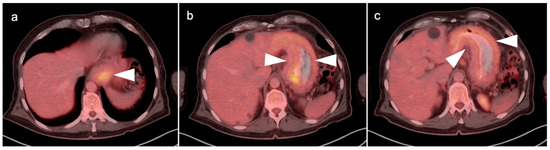

4. Hepatocellular Carcinoma